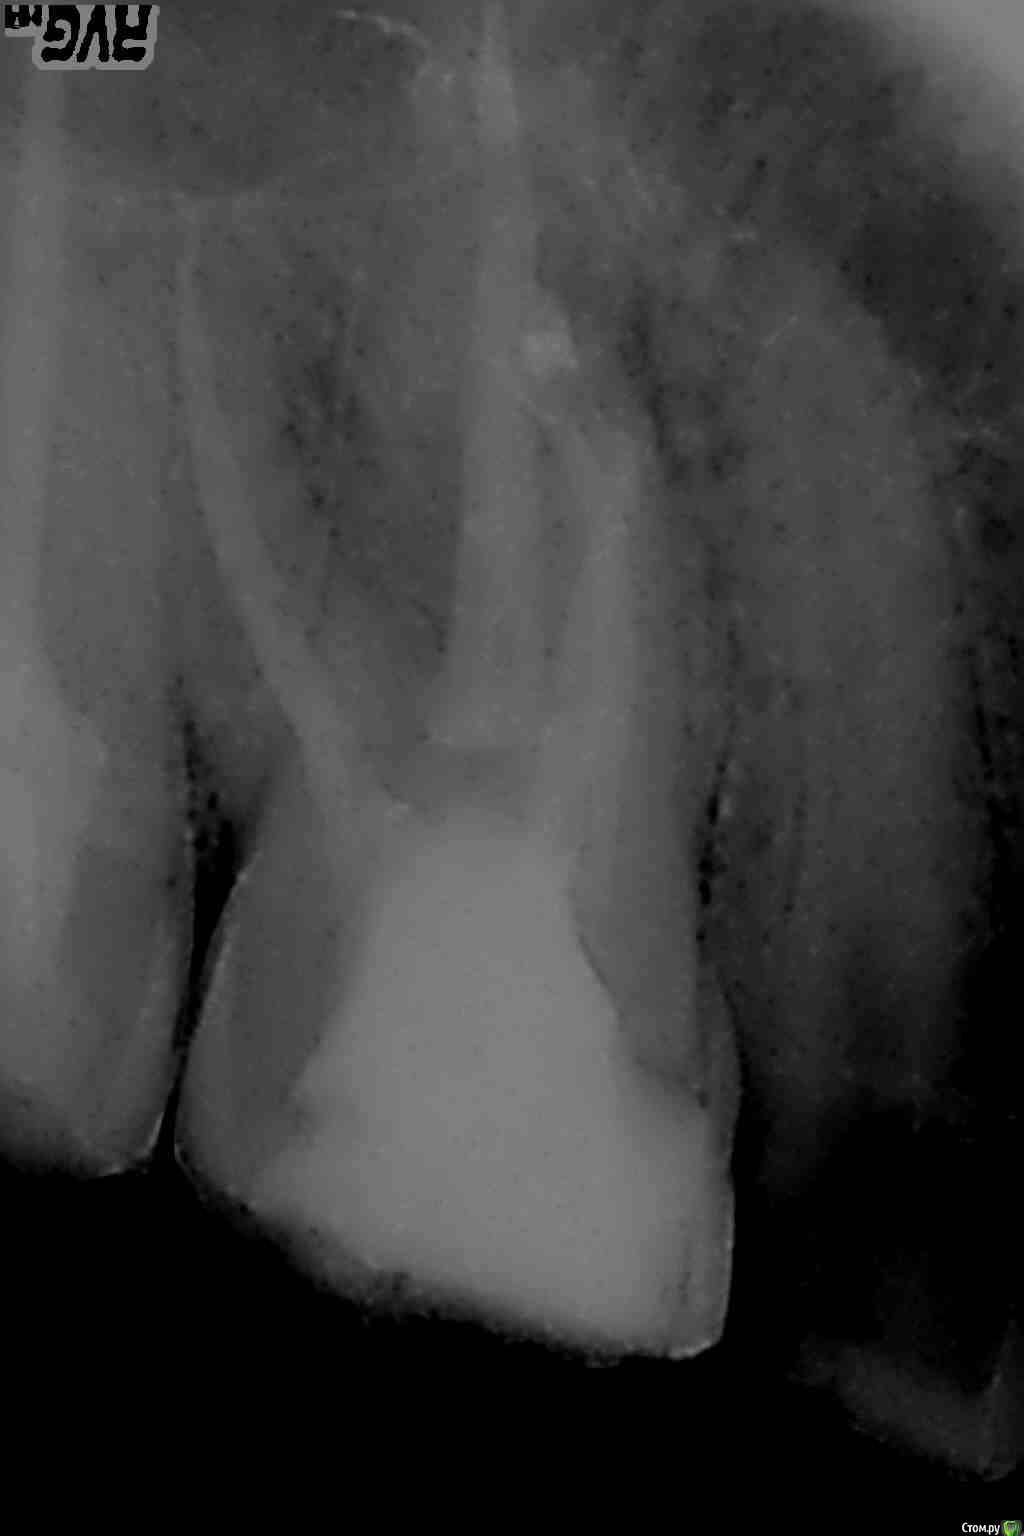

St. Опубликовано 22 декабря, 2015 Поделиться Опубликовано 22 декабря, 2015 От холодного зуб без нервов болеть не может - если нерва нет, то реагировать там на холод и тепло нечему. При постукивании и накусывании после недавнего лечения каналов какое-то время может оставаться чувствительность, обычно до 2 недель, но бывает немного дольше, это нормально.По Вашему снимку я бы рекомендовала обязательно и в ближайшем будущем удалить зуб мудрости внизу справа, полечить кариес в 34(следующий за клыком внизу слева). И когда зуб перестанет реагировать на постукивание - одеть на него коронку и обсудить необходимость коронок на другие боковые зубы без нервов. 1 Ссылка на комментарий

bozz903 Опубликовано 19 марта, 2016 Автор Поделиться Опубликовано 19 марта, 2016 Здравствуйте. С наступлением весны все тот же 16 зуб стал реагировать на температуру очень сильно. Также ноет сам по себе периодически. Боль не похожа на гиперчувствительность эмали.Сделал новые снимки. Что нибудь можно сказать по сравнение с теми, которые прикреплены в первом моем сообщении? Ссылка на комментарий